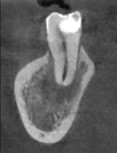

將牙齒拔出後,在口外做根管治療、並且切除牙根末端神經較複雜處。

醫師在口外對牙齒完成治療後,再將牙齒植入同一位置

治療前X光片。